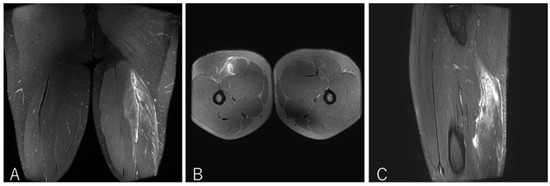

Impact of Proximal Conjoint Tendon Injury on Return to Play in the BF–ST Complex: A Prospective MRI-Based Study

by Makoto Wada, Takumi Okunuki, Takeshi Sugimoto, Yasuhito Tanaka and Tsukasa Kumai

Background/Objectives: Proximal hamstring injuries involving the biceps femoris–semitendinosus (BF–ST) conjoint tendon (CT) often exhibit delayed healing, yet the prognostic significance of CT involvement and intratendinous injury morphology has not been fully clarified. This study aimed to determine whether full-layer CT injury, particularly bilateral [...] Read more.

Background/Objectives: Proximal hamstring injuries involving the biceps femoris–semitendinosus (BF–ST) conjoint tendon (CT) often exhibit delayed healing, yet the prognostic significance of CT involvement and intratendinous injury morphology has not been fully clarified. This study aimed to determine whether full-layer CT injury, particularly bilateral involvement in Zone C, prolongs return-to-play (RTP) in competitive rugby athletes. Methods: This prospective study evaluated 41 university rugby players with acute BF–ST complex injuries using clinical examination, ultrasonography, and MRI. Injuries were classified by Type (I: full-layer CT; II: BFLH-only; III: ST-only), Zone (A–E), and Grade (0–3). RTP was defined as unrestricted return to team training or match play. Group differences were analyzed using ANOVA or non-parametric tests with appropriate post hoc corrections. Results: Type I injuries required significantly longer RTP (11.4 ± 4.8 weeks) than Type II (5.3 ± 2.4 weeks) and Type III (4.0 ± 1.7 weeks), confirming the strong impact of CT involvement on prognosis. In Zone C, bilateral full-layer CT involvement was associated with an approximately twofold longer RTP duration compared with unilateral BFLH-side injuries, indicating that intratendinous tissue disruption influences recovery. These findings highlight the importance of early MRI-based assessment to identify clinically relevant tendon involvement patterns. Conclusions: Full-layer CT injuries, particularly bilateral intratendinous patterns in Zone C, markedly prolong RTP compared with isolated BFLH or ST injuries. An MRI-based classification incorporating injury type, zone, and extent of CT involvement provides clinically valuable prognostic information and may enhance RTP decision-making. Full article

Show Figures

Figure 1